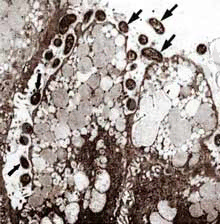

Микроскоп астындағы Helicobacter pylori көрінісі

Электронды микроскоп астында асқазанның шырышты қабатының Хеликобактериймен зақымдалған аймағының бейнесі